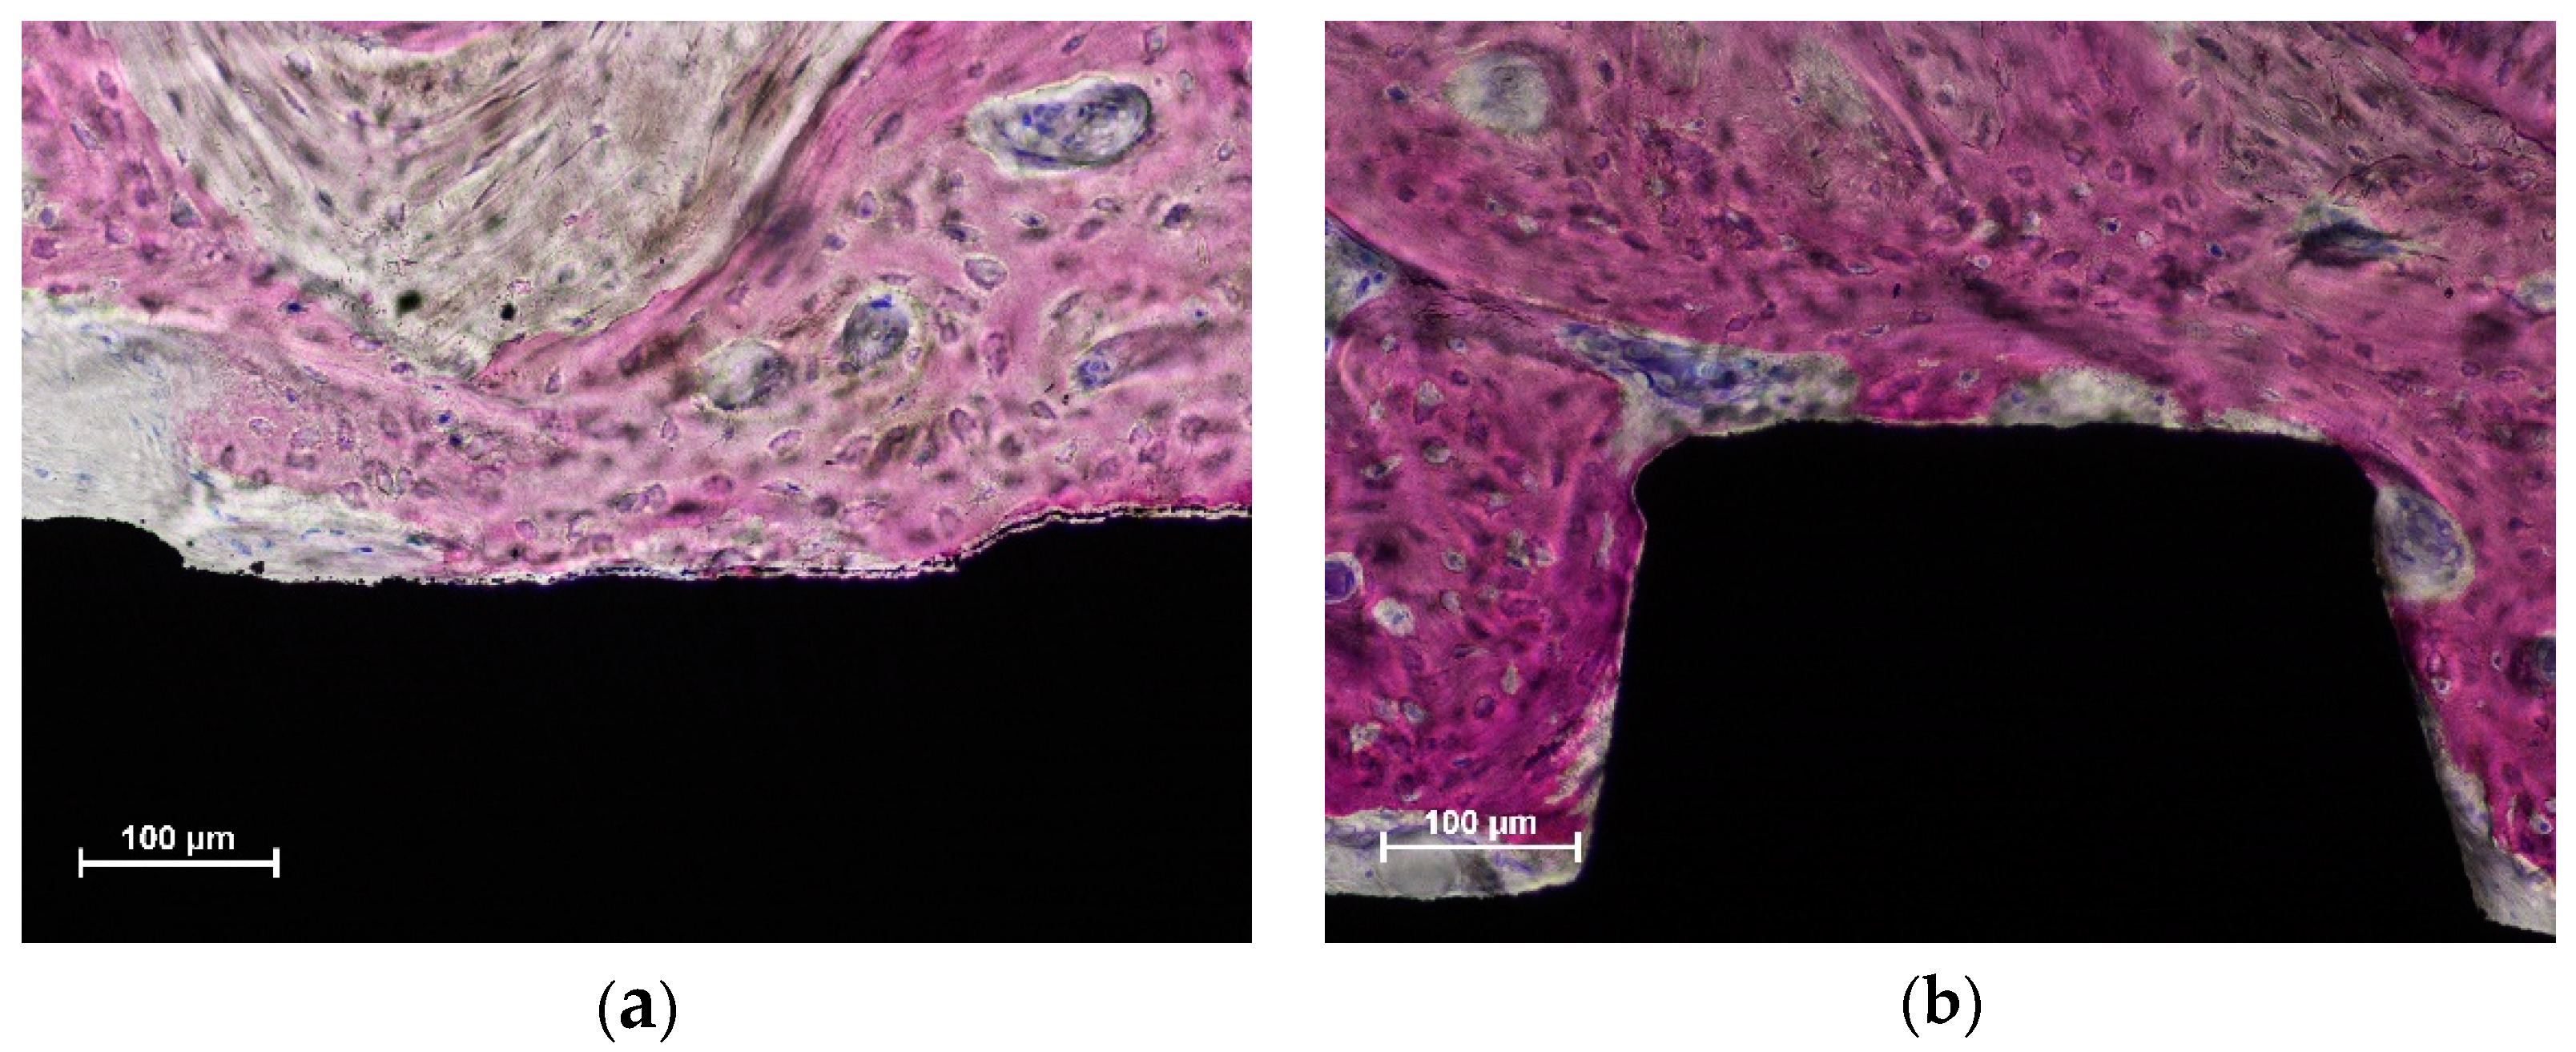

3.2. Histomorphometric Description

3.3. Histometric Evaluations—Tissues in Contact with the Implant Surface